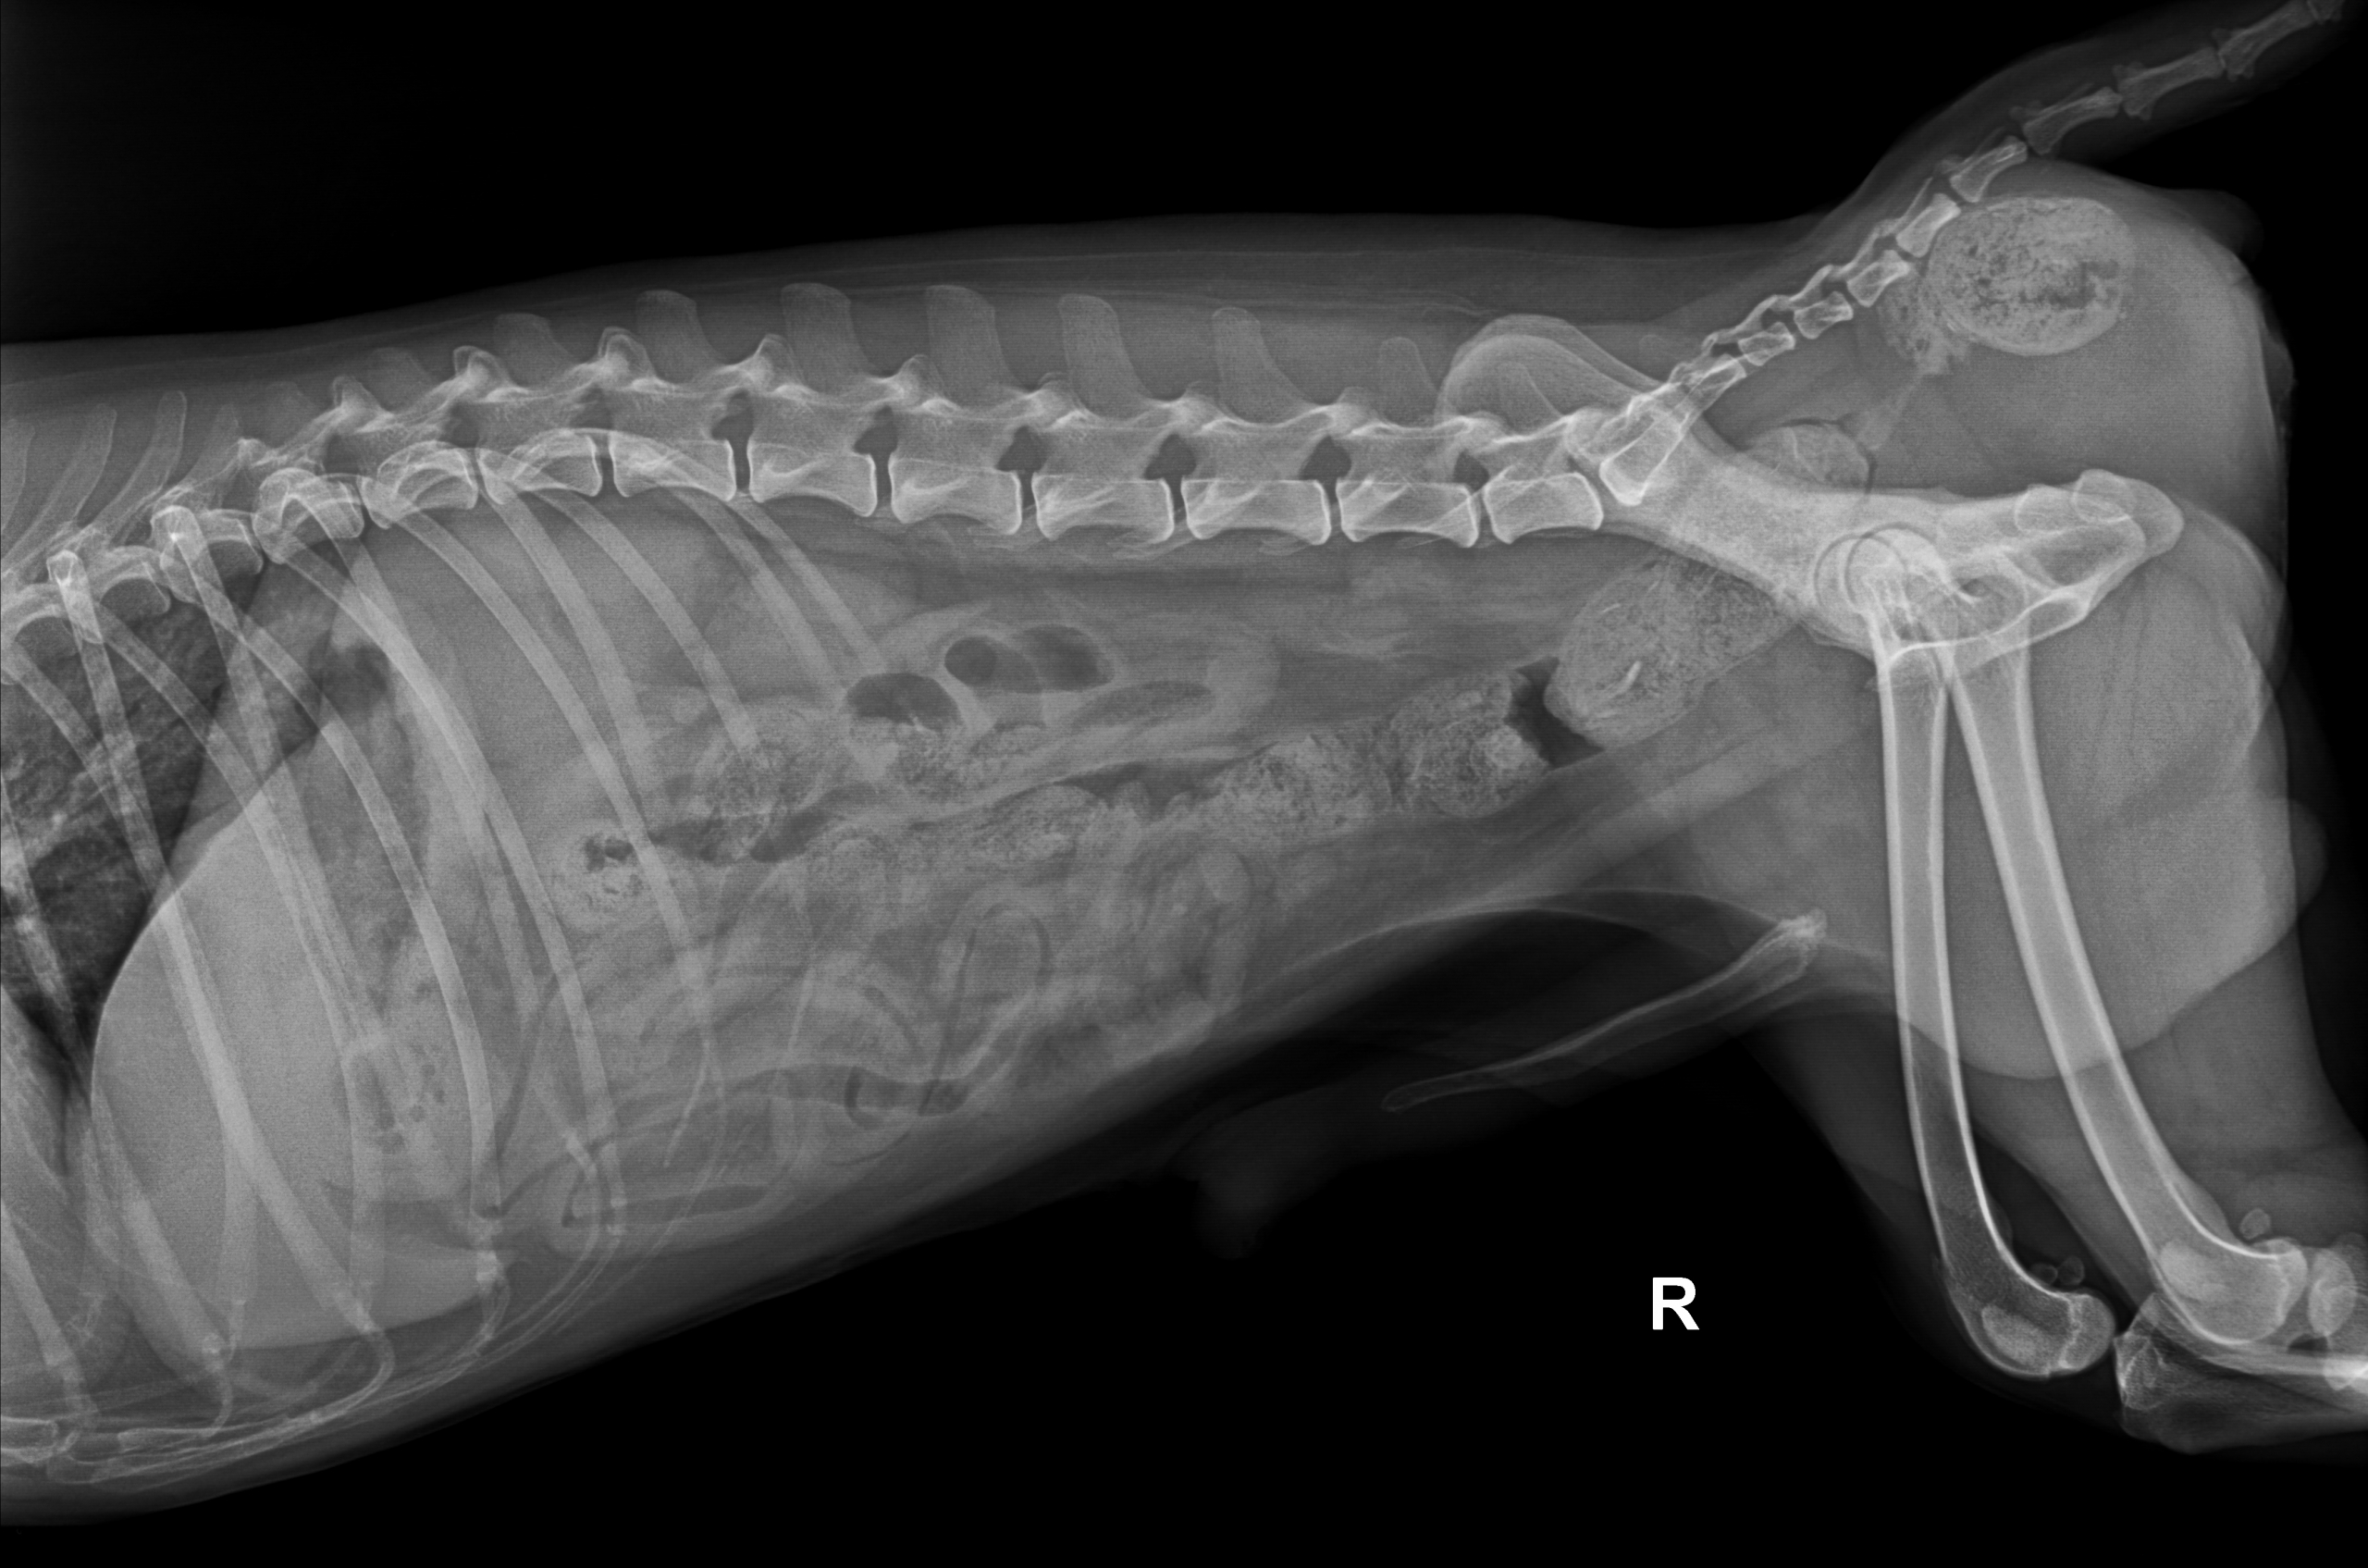

Fallbericht: Koprostase mit Perinealhernie

Milou wurde am 13.07.2022 in der Notaufnahme vorstellig, weil er keinen Kot mehr absetzen konnte und sich eine Ausbeulung neben dem After zeigte. In den vorherigen Tagen wurden Knochen gefüttert. Im Röntgen zeigte sich eine hochgradige Verstopfung mit hartem Knochenkot, der sich bereits neben dem D…